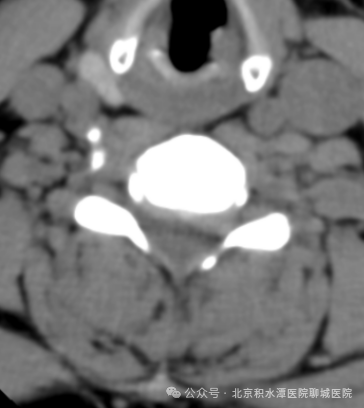

术前影像:C5/6椎间盘向左后方突出,压迫神经根

术后影像:去除C5/6左侧椎管背侧少量骨质

进行减压并摘除突出的间盘组织